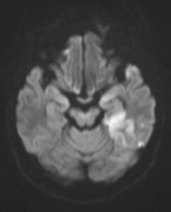

张女士被紧急送往附近医院,头颅磁共振检查明确诊断为急性脑梗死。

左侧大脑中动脉和颈内动脉均已闭塞,相当于左侧大脑半球几乎断了供血,手术指征明确。

5 分钟后,张女士被推进介入手术室,急诊脑血管造影进一步确认了血管闭塞情况。